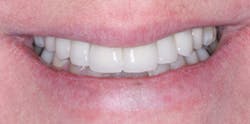

FIG. 10 -- A happy patient. This patient could not have screws through the crowns because the angulation of the implant placement would have led to screw holes coming through the facial surfaces of the crowns.